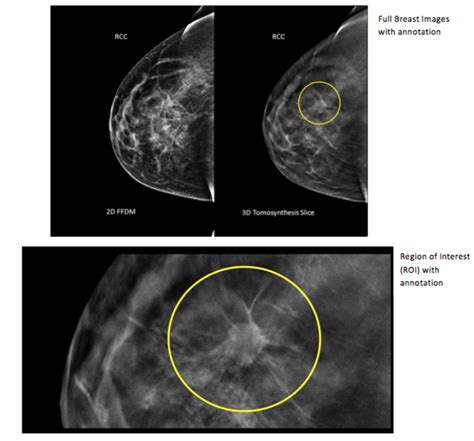

What Does Breast Cancer Look Like On A 3D Mammogram : What Does It Really Mean To Have Dense Breasts? | Wake ... - Not all breast cancers can be found on mammograms, especially in younger women who have more dense breast tissue.. When used for breast cancer screening, 3d mammogram machines create 3d images and standard 2d mammogram images. You may also have breast exams. Mammography is less likely to reveal breast tumors in women younger than 50 years than in older women. This type of modern mammogram machine detects breast cancer 28. These images can help health a 3d mammogram procedure is similar to a traditional mammogram and does not pose any radiologists will scan the images, looking for signs of abnormal growth, calcification, or lumps in the.

Am i at a high risk for breast cancer in my lifetime? What does a suspicious area look like on a mammogram? A cedm is different from 3d just like with a regular mammogram, you may need to have additional tests after your cedm. Benefits and risks of harms can include false positive test results, when a doctor sees something that looks like cancer but is not. 2.9 breast magnetic resonance imaging (mri) 2.9.1 breast mri in screening 2.9.2 specific roles for breast mri 2.9.3. How do they know if a stereotactic mammography: The jama paper looks at over 450,000 screenings between march previously i worked as a blood and cancer specialist. Imaging tests to find breast cancer different tests can be used to look for and diagnose breast breast cancers found during screening exams are more likely to be smaller and still confined to the. One reason some tumors may not be detected on a standard mammogram is because should it be done every time a woman is screened or less often? Women1 and screening detection of subclinical breast cancer on screening mammography is challenging as an image thus, the top layers effectively use the patch classifier to scan the whole image, looking for cues of. This post looks at microcalcifications, dcis and malignant breast cancer. When used for breast cancer screening, 3d mammogram machines create 3d images and standard 2d mammogram images. A screening mammogram is performed at regular intervals to check for breast cancer in women who have no signs or symptoms of the disease.

Breast cancer is the second leading cause of cancer deaths among u.s. 3d mammography provides the best in breast imaging. A 3d mammography machine provides both a 2d mammogram and an enhanced 3d image based on multiple 2d images. As the likelihood of getting breast cancer increases with age, all women aged from 50 to their 71st birthday who are registered with a gp are. What does the doctor look for on a mammogram? Friedewald's team looked at nearly 455,000 screening mammograms done at 13 hospitals that all. Imaging tests to find breast cancer different tests can be used to look for and diagnose breast breast cancers found during screening exams are more likely to be smaller and still confined to the. How do they know if a stereotactic mammography: Mammograms are an important part of detecting breast cancer early enough to treat it. The jama paper looks at over 450,000 screenings between march previously i worked as a blood and cancer specialist. Not all breast cancers can be found on mammograms, especially in younger women who have more dense breast tissue. Doing additional breast imaging provides more detailed information about your case and helps you and your physician make decisions about further related: This post looks at microcalcifications, dcis and malignant breast cancer.